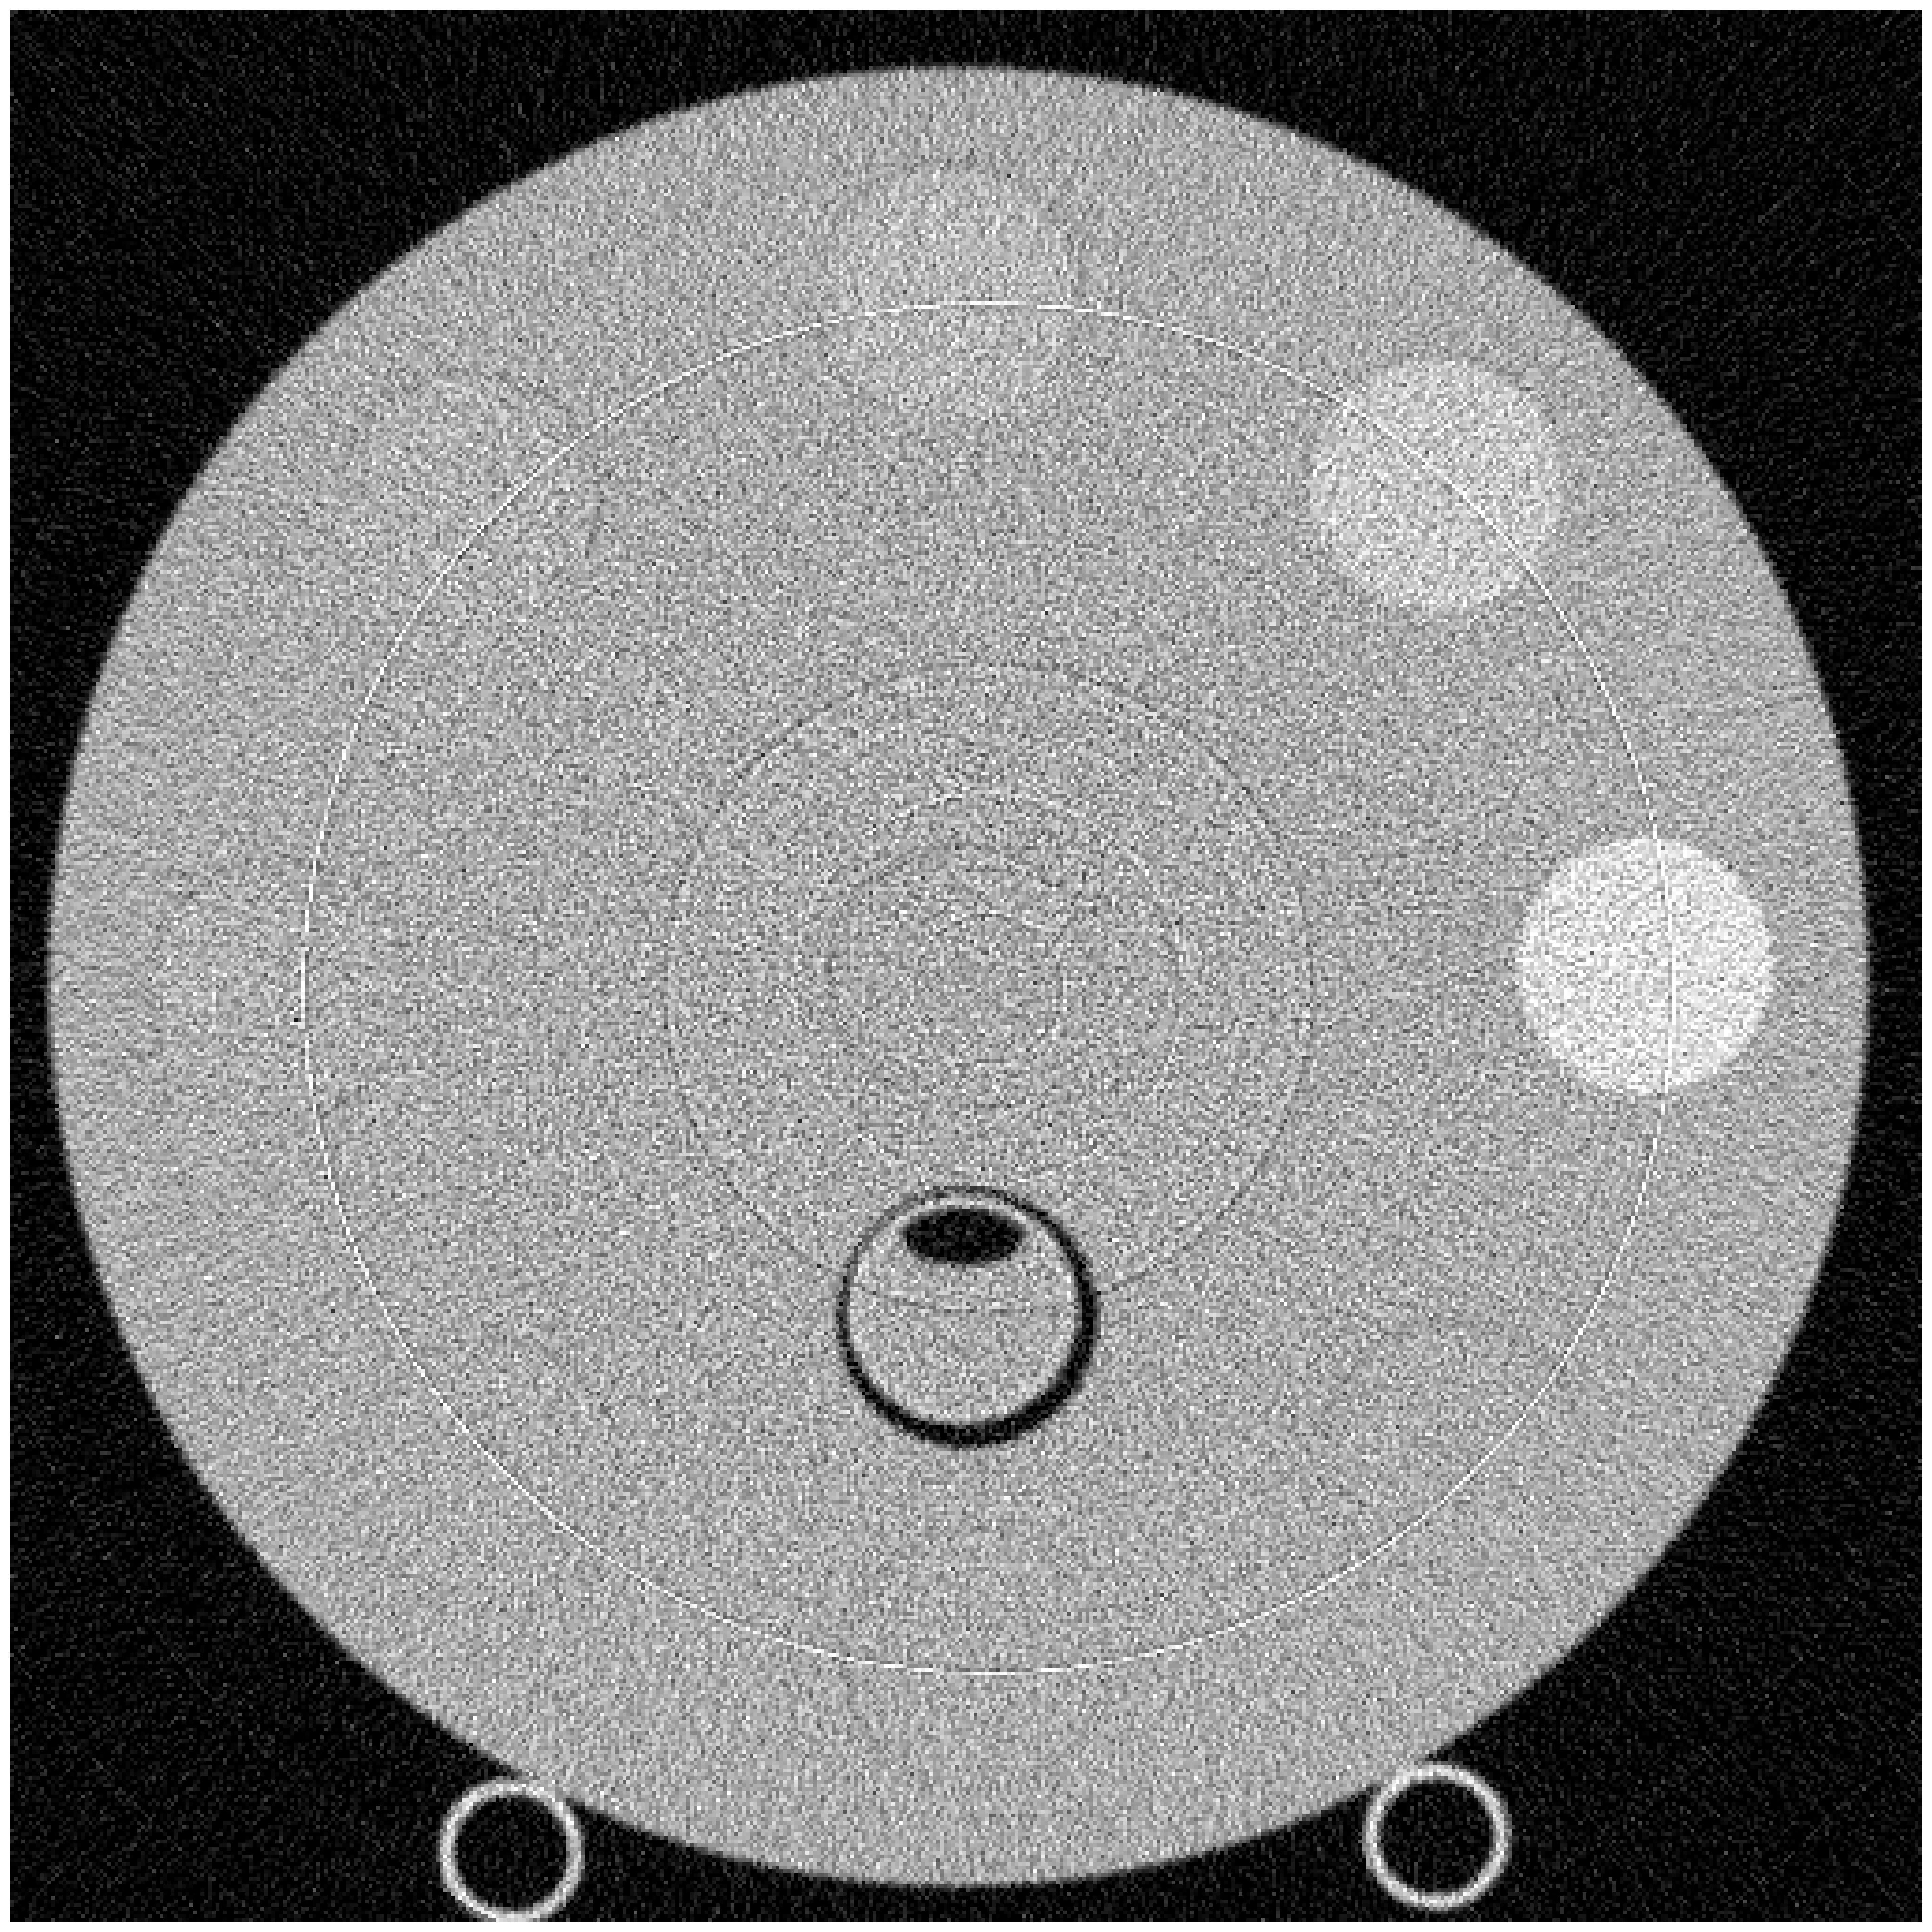

For experiments with simulated data, we use a phantom with inserts of densities close to water to evaluate performance on low-contrast targets. We scanned the phantom times at 120 kVp, 400 mA at 1 s per rotation for 1000 views and averaged the reconstruction results. The scan is reconstructed for the image size of and display-field-of-view (DFOV) of 25.6 cm.

The left and right panels of Figure 2 show the baseline MLE and proposed algorithm reconstructions of the simulated data, respectively. The reconstruction is shown in Hounsfield units (HU), modified so that air is 0 and water is 1000, with a center of 1000 HU and a window width of 20 HU. The result using our proposed method uses a simple linear filter as a prior but is still able to distinguish inserts with less than deviation from water density, even for very small feature lengths.